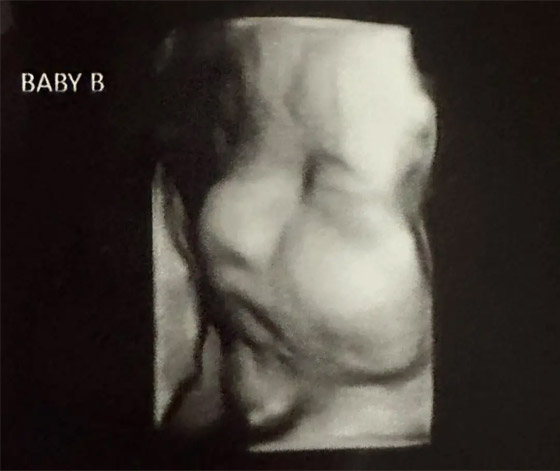

وأشارت إلى أن ذلك يعتبر "تشوّهاً خلقيا" يطال هذا العضو، تشير التقديرات إلى أن نحو 0,3% من النساء يعانين من هذه الحالة. وخلال فحص روتيني بالموجات فوق الصوتية في أيار/مايو الفائت، علمت هاتشر، وهي أم لثلاثة أبناء، أنها حامل بتوأم، وأن كل جنين منهما ينمو في أحد رحميها. كما كتبت عبر إنستغرام "لقد أصبنا بالذهول! وخلال أول فحص بالموجات فوق الصوتية، ضحكنا كثيراً".

وتعود الحالة الأكثر شهرة إلى امرأة بنغلاديشية تُدعى عريفة سلطانة وعمرها 20 سنة، أنجبت عام 2019 طفلين بفارق 26 يوماً بينهما. وكان الرضيعان بصحة جيدة. وأملت هاتشر أن تتمكن من ولادة الطفلين بشكل طبيعي في الموعد المحدد لها، وهو يوم عيد الميلاد. في حين تبدو صحة الجنينين جيدة حتى اليوم.